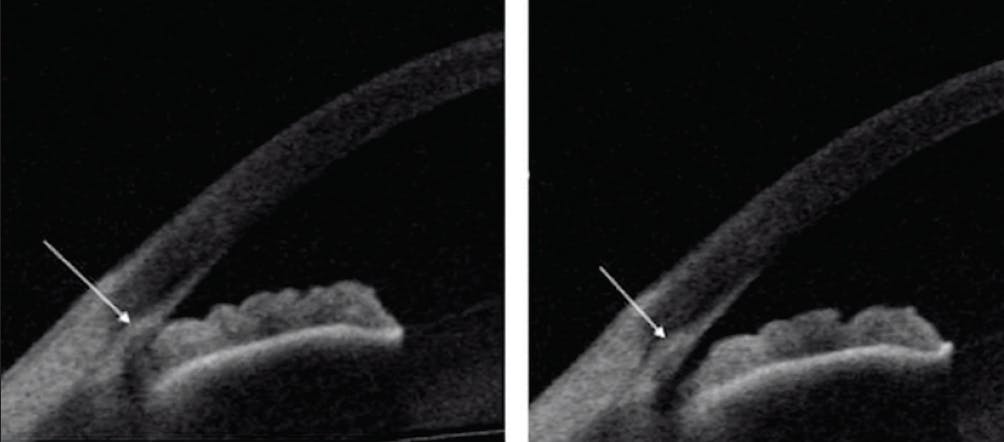

Results from the Zhongshan Angle Closure Prevention (ZAP) trial2 and the Effectiveness of Early Lens Extraction for the Treatment of Primary Angle-Closure Glaucoma (EAGLE) study3 suggest that lens extraction may be the best intervention for patients with angle closure. The Investigating Management of Primary Angle Closure and Treatment (IMPACT) study4 and Koh et al5 used gonioscopy, nerve-based imaging, functional testing, and AS-OCT parameters to evaluate patients with narrow occludable angles and predict which were likely to progress. Studies such as these have contributed valuable information on how best to intervene in these cases; the challenge is identifying patients for treatment. Fortunately, AS-OCT can be used in the clinic to visualize several anatomic landmarks and to determine whether the anterior chamber angle is open or closed. AS-OCT can also be used to assess the effects of interventions such as laser peripheral iridotomy and lens extraction in patients with angle closure (Figure 2).

Figure 2. AS-OCT can be used to assess the effects of laser peripheral iridotomy in patients with angle closure. Reprinted with permission from Kansara S, Blieden S, Alice C, et al. Anterior chamber angle anatomy in primary angle closure spectrum eyes. J Glaucoma. 2016;25(5):e469-e474.